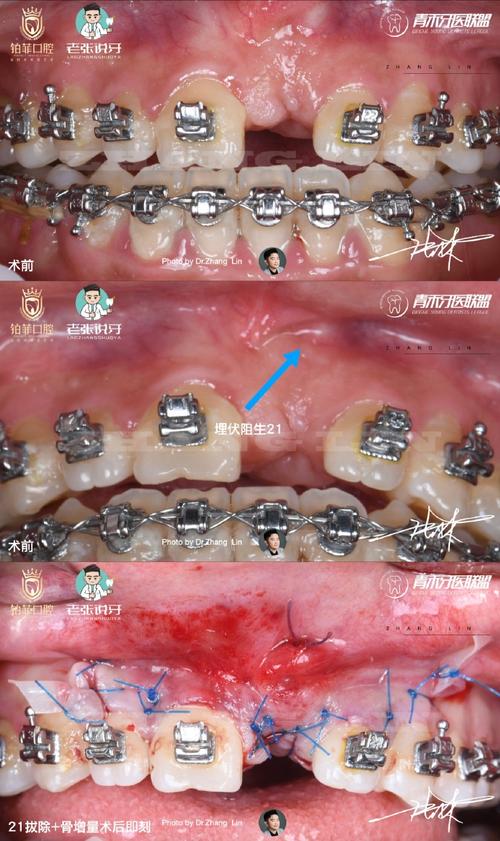

| 牙槽突植骨术 | 唇腭裂术后牙槽突裂隙、牙齿缺失区骨量不足 | 取自体骨(如髂骨)或人工骨植入裂隙 | 3个月内避免植骨区受力,正畸器轻力移动 |